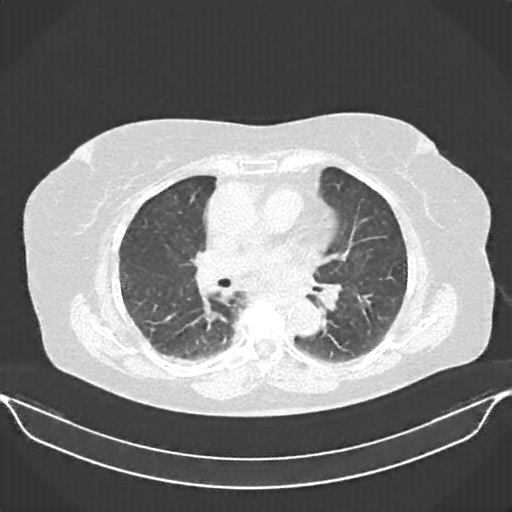

Original VENOUS CT scan

No window - Raw intensity values

Lung window (WL -600, WW 1500 β†’ Low βˆ’1350, High +150)

Mediastinum window (WL 40, WW 400 β†’ Low βˆ’160, High +240)